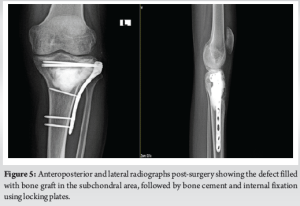

The cavity formed was further enlarged using a high-speed burr, ensuring the surrounding tissue remained uncontaminated. Sufficient samples were collected for histopathological analysis. Pulsatile lavage was given, facilitating the exposure of raw cancellous bone. Subsequently, phenol was instilled; as an adjunct, the remaining cavity was filled with bone cement, pieces of iliac crest graft were then placed in the subchondral region, followed by the application of a gel foam (a biodegradable, non-toxic gel made from human fibrinogen and thrombin) layer beneath them; the bone was then stabilized by internal fixation [Fig. 5] with a proximal tibia locking plate. A drain was inserted and the wound was sutured.